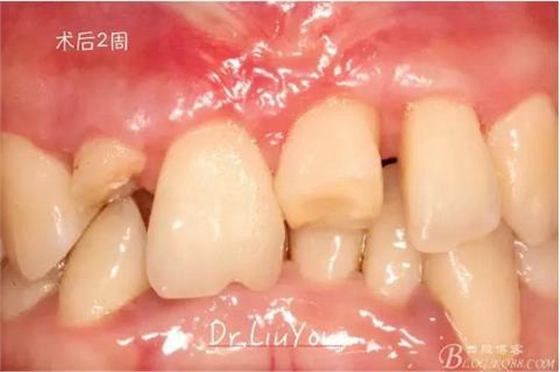

骨塊固定兩周后復(fù)查,如上圖

松動牙固定一月后拆除,A1-B2無明顯動度,但牙齦紅腫加重,給予全口齦上下潔治刮治術(shù),上藥,醫(yī)囑加強(qiáng)口腔衛(wèi)生,氯己定漱口液含漱。

術(shù)后兩周復(fù)查,牙齦紅腫明顯好轉(zhuǎn),探診不出血,但是此時A1唇側(cè)牙齦角形退縮1.5mm,B1唇側(cè)牙齦退縮3.5mm,B1遠(yuǎn)中牙齦乳頭萎縮明顯,B2近中牙齦萎縮約1mm,且A1B1B2牙齦退縮處角化牙齦幾乎缺失,同時上唇系帶直接牽拉于B1齦緣?;颊邽楦咝€女性,露齦笑,由于存在前牙區(qū)牙齦的高度嚴(yán)重不對稱及前牙牙冠過長的問題,因此嘗試通過膜齦手術(shù)改善患牙牙齦退縮。通過術(shù)前分析,A1唇側(cè)牙齦退縮屬于Miller分類第一類, B1唇側(cè)牙齦退縮屬于Miller分類第3類(B1遠(yuǎn)中牙齦乳頭為2類,Nordland and Tarnow分類法),B2唇側(cè)牙齦退縮屬于Miller分類第3類,由于擬采用冠向復(fù)位瓣的方式治療牙齦退縮,因此需要先行上唇系帶修整術(shù),解除上唇系帶帶來的過大牽引力。

潔治刮治后2周,如上圖